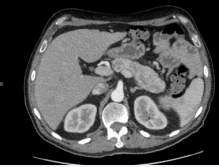

His oral glucose tolerance confirmed him to be diabetic. His CT scan showed a large pancreatic mass with involvement of lymph nodes and local infiltration (Figure 2,3).

Figure 2 Pancreatic mass with lymph node involvement.

Figure 3 Pancreatic mass with local tissue invasion.